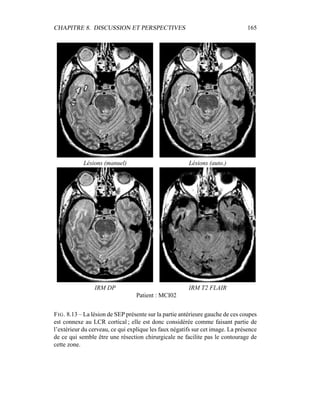

0

0.002

0.004

0.006